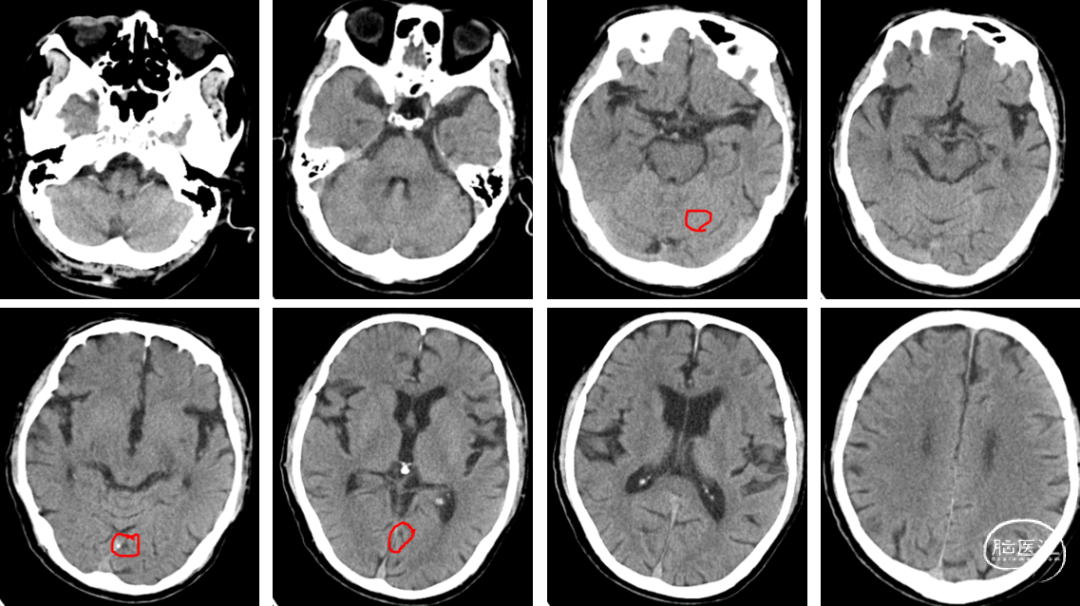

头颅CT(2024-07-25,外院):双侧基底节区,放射冠腔隙性脑梗死。

1、RCCA分叉处见一枚隆起性混合回声斑块,大小约14*2.7mm;

2、RCCA分叉处至ECA起始处见一枚不均质回声斑块,大小约16.2*7.6mm,该处狭窄约80%;

3、LCCA壁上见数枚隆起性混合回声斑块,其中左侧颈总动脉分叉处壁上一枚大小约6.3*2.6mm,双侧颈动脉粥样硬化,右侧颈总动脉分叉处至颈外动脉起始处狭窄。

患者取平卧位置,常规消毒、铺巾和局麻右侧腹股沟下穿刺点后,穿刺置入5F动脉鞘,再以5F单弯行选择性脑动脉造影。造影示:II型主动脉弓,右侧颈内动脉C1段重度狭窄。

左侧颈动脉未见明显异常。

造影显示左侧椎动脉V1段中重度狭窄。

使用雅培Workhorse保护伞导丝先行通过病变狭窄处,随后将Emboshield Nav6保护伞沿导丝推送经过C1端弯曲处。借助Nav6保护伞的支撑,推送6F 115cm中间导管至C1远端,利用特洛伊木马技术将Nav6保护伞输送并放置于颈内动脉C1段。回撤中间导管,在透视状态下释放Nav6保护伞,Nav6圆周骨架在透视下显影清晰,定位准确。

将中间导管撤至颈总动脉,通过Workhorse导丝送入4mm*20mm球囊至右侧颈内动脉狭窄病变处,准确定位后以适当压力预扩狭窄病变,造影示狭窄改善不明显。撤出球囊,再次通过Workhorse导丝送入5mm*30mm球囊至狭窄病变处进行扩张,造影提示狭窄稍改善。

考虑到靶血管较迂曲,拟使用中间导管进行支架释放。在Workhorse导丝引导下,将中间导管通过迂曲段,经由中间导管送入8mm*40mm颈动脉支架至右侧颈内动脉狭窄处。回撤中间导管至颈总动脉后,在透视状态下准确释放支架。

造影显示残余狭窄小于30%,未进行后扩张。术后造影显示狭窄解除,支架置入部位满意,血流较术前明显改善。使用中间导管将Nav6保护伞顺利回收后,对股动脉穿刺点进行止血,患者安返病房。